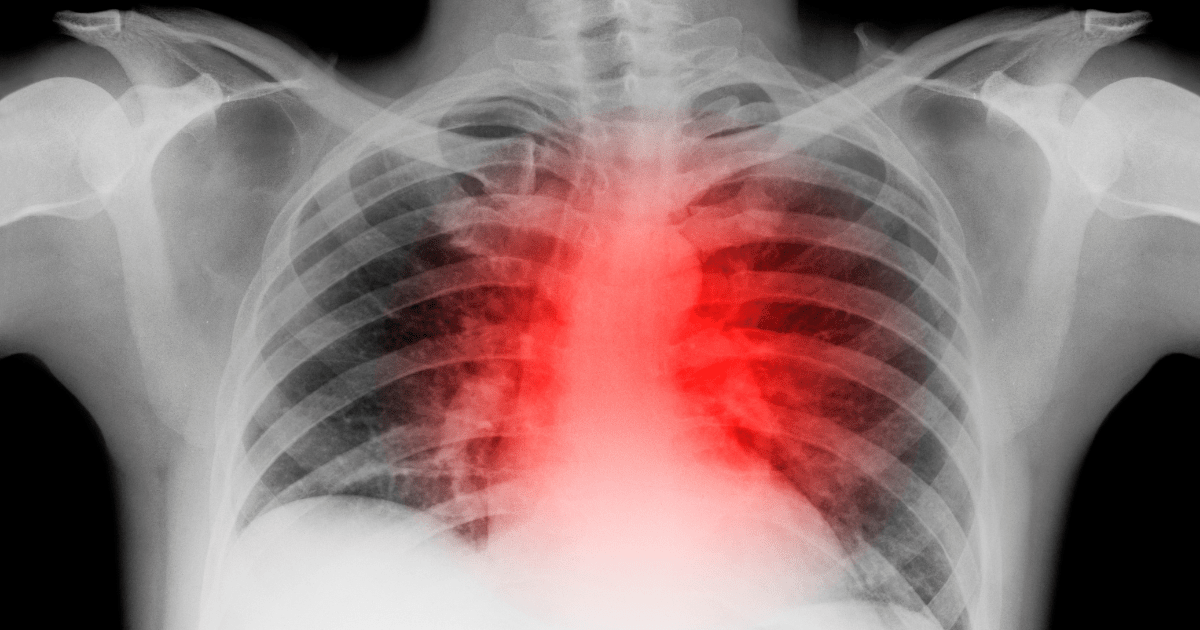

Heart attacks are the world’s leading cause of death, yet the few treatments available are often expensive and inaccessible. Although that’s been the case for years, the World Health Organization warned back in 2020 heart disease numbers were still on the rise.

The gene editing technique will initially be tried on individuals who have already suffered a heart attack for a hereditary condition that impacts as many as 31 million people globally. Verve uses CRISPR gene editing, a powerful but ethically complex gene tool. If this round of testing goes well, Verve may expand to larger groups of people.